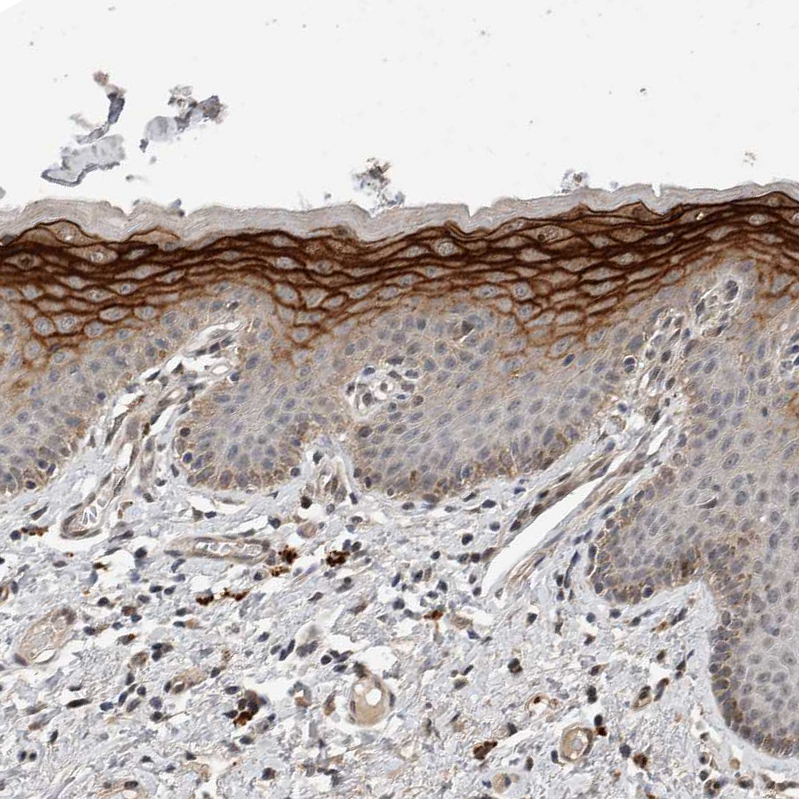

Immunohistochemical staining of human esophagus shows strong membranous positivity in squamous epithelial cells.